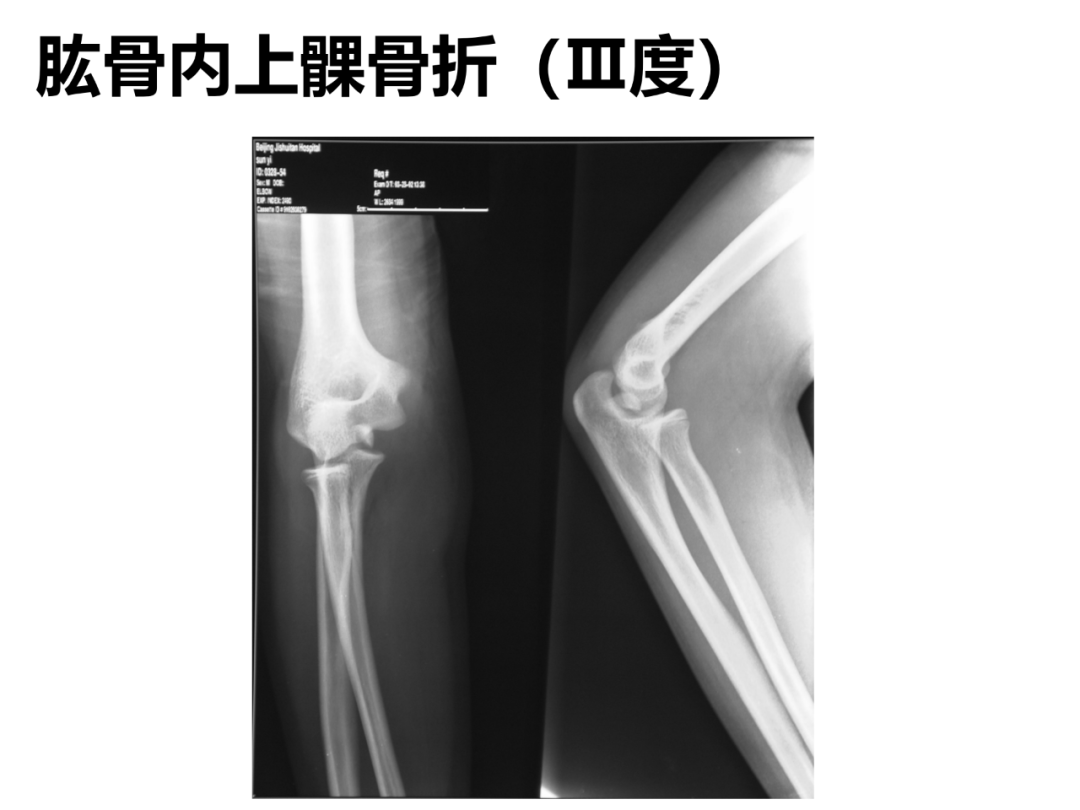

小儿骨科X线片汇总,临床读片宝典!